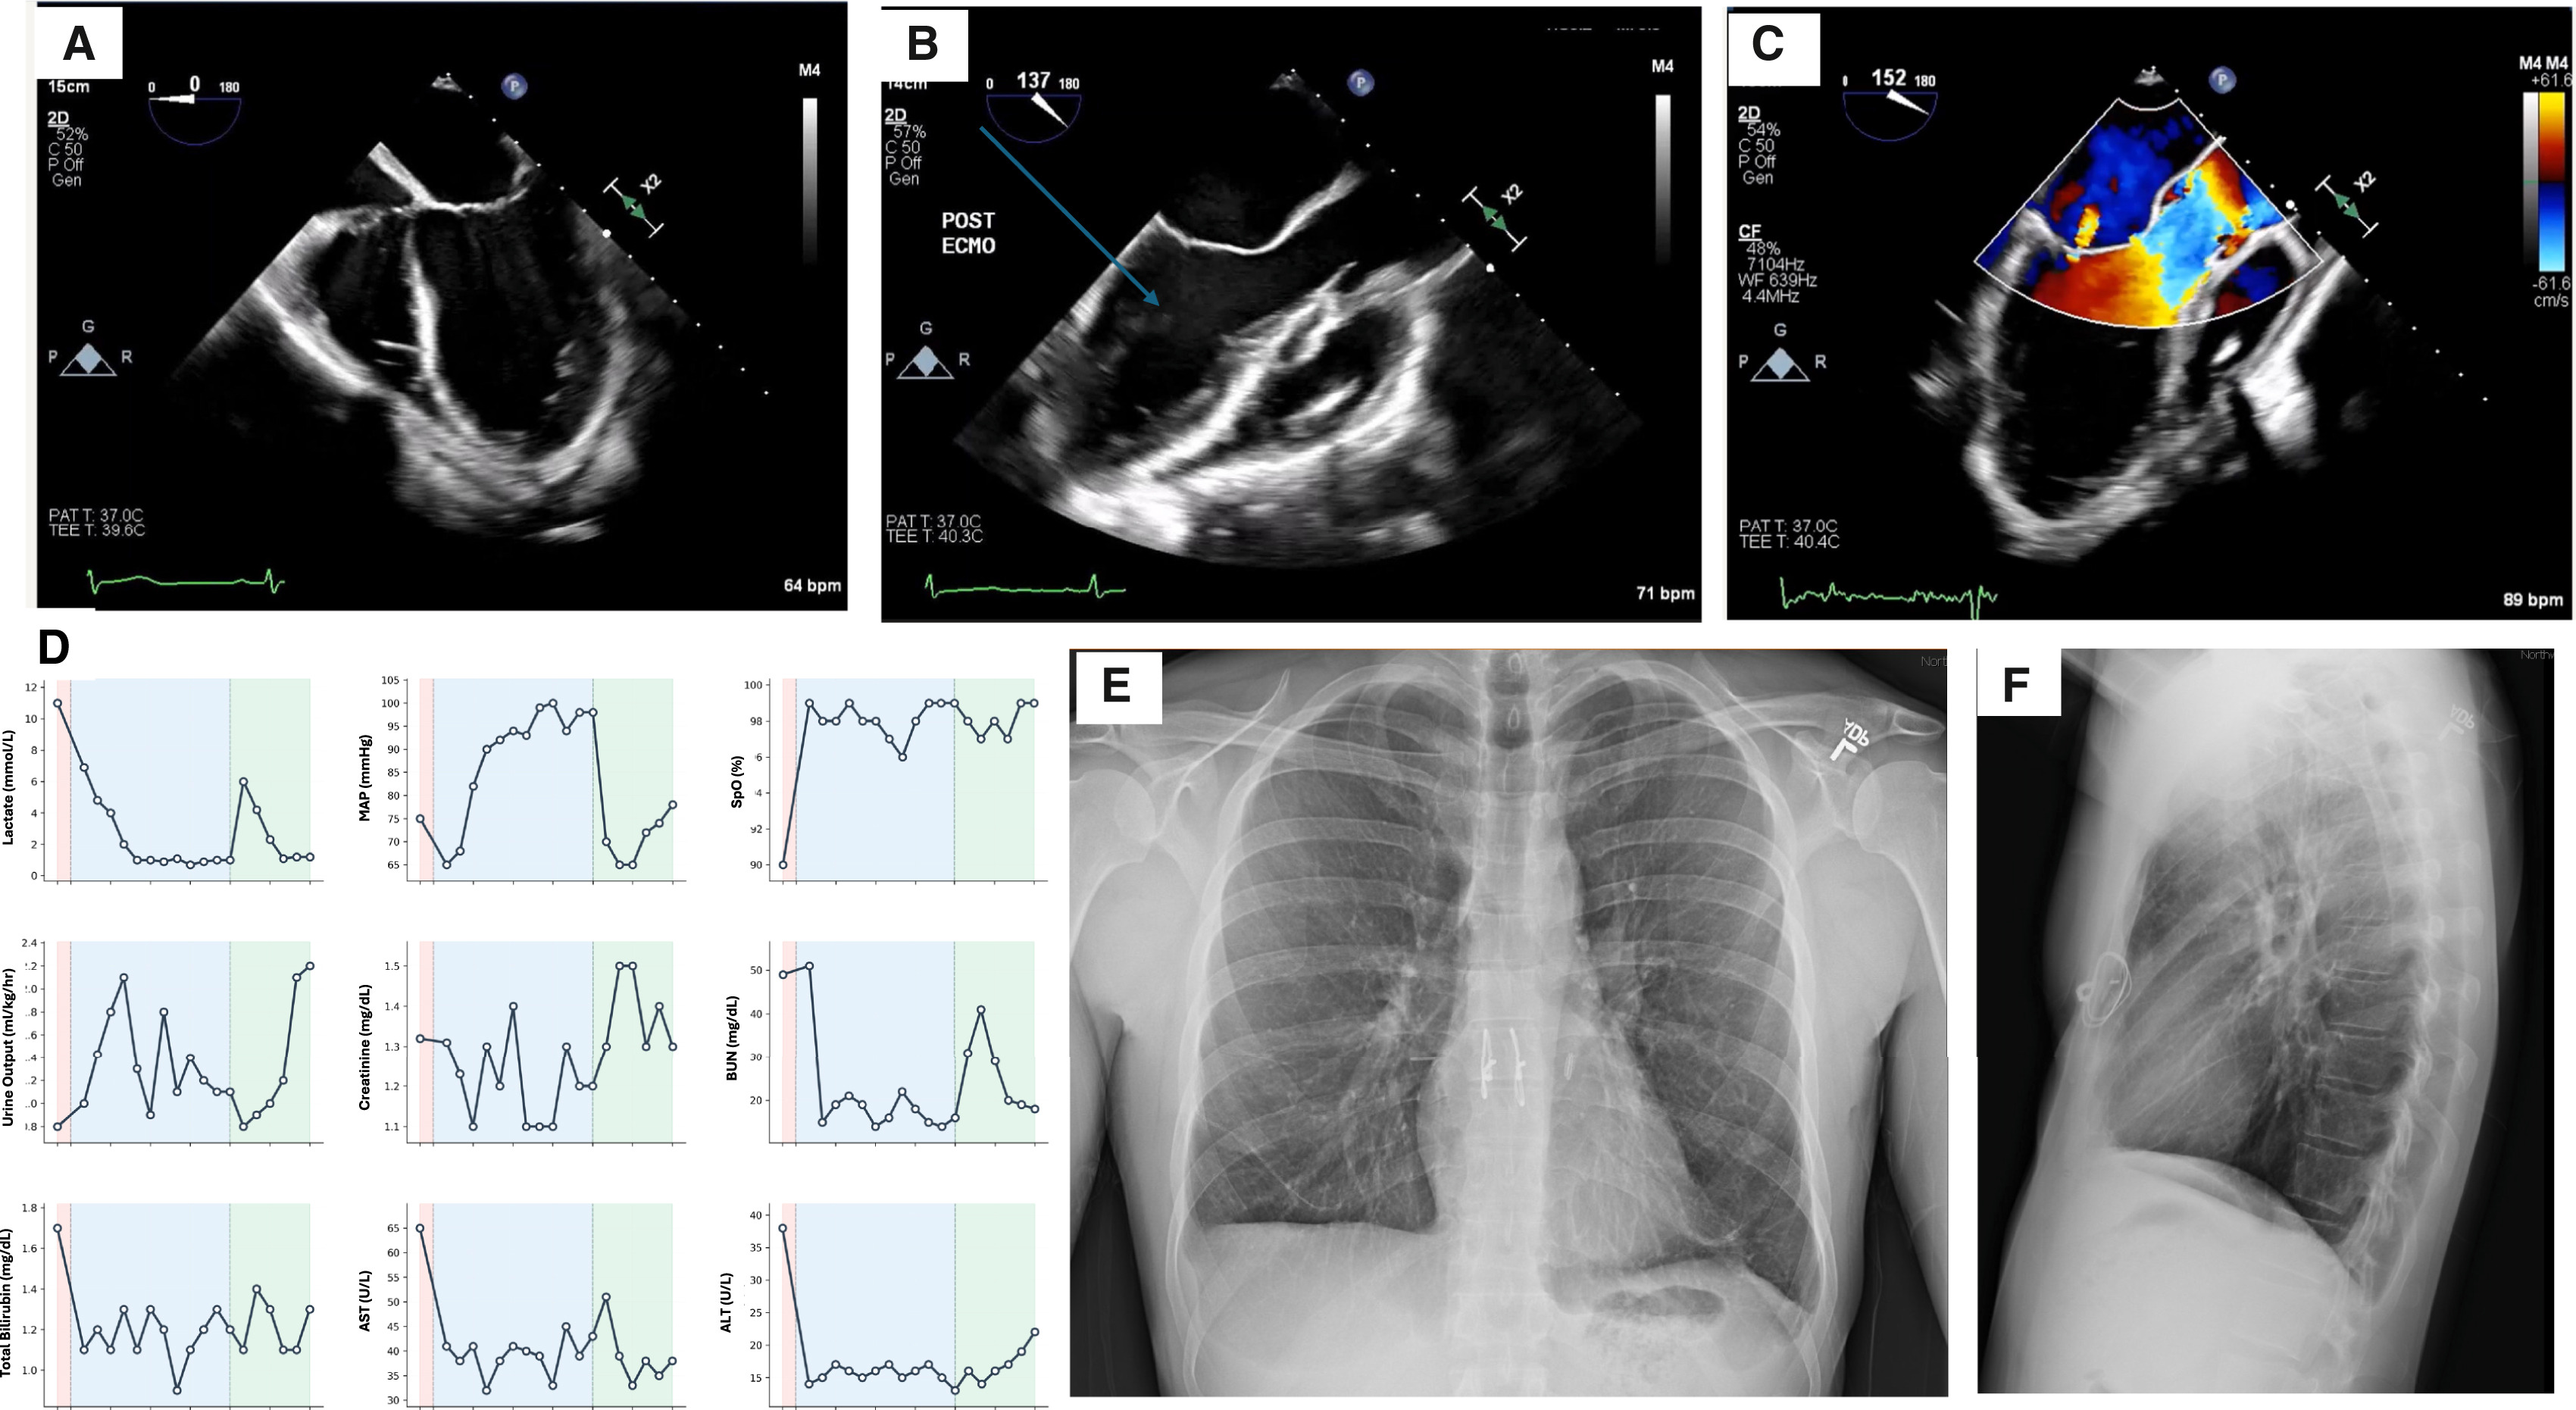

However, removing both lungs creates a massive void in the circulatory system. To solve this, the team developed an extracorporeal Total Artificial Lung (TAL) system. This custom-engineered circuit did more than just breathe for the patient, rather, it replaced the entire internal plumbing of the chest.

The custom TAL system functioned as a complete circulatory bridge, using specialized shunts and external units to oxygenate the blood and scrub carbon dioxide. More than just a breathing machine, it featured dual return lines that carefully regulated blood flow back to the heart, ensuring the organ remained stable and continued to pump naturally even with the lungs missing.

The results were immediate. Once the infected lungs were removed, the source of the sepsis vanished. Within 48 hours, the patient's blood pressure stabilized, his kidney function returned to normal, and he no longer required medication to keep his heart beating.